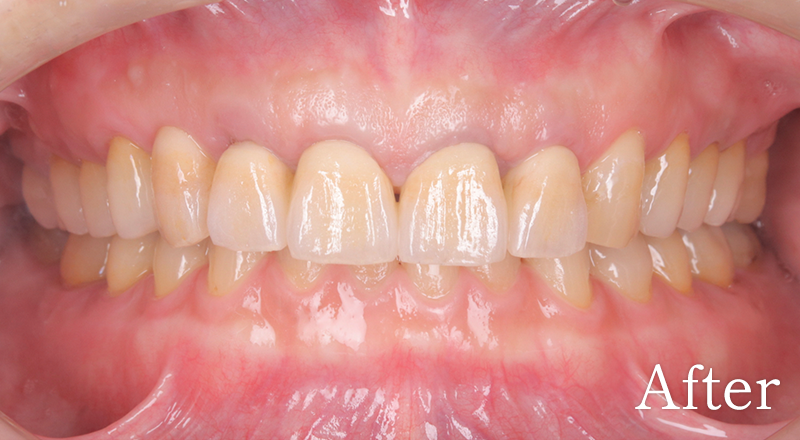

CASE3

主訴 奥歯でうまく噛めない

治療内容 上下顎臼歯部インプラント、咬合再構成、セラミック治療

治療期間 約2年

費用 診断料:22万円(税込)

上顎顎臼歯部インプラント埋入手術:22万円(税込)×6本

セラミック補綴:22万円(税込)×6本

セラミック治療:11万円(税込)×12本